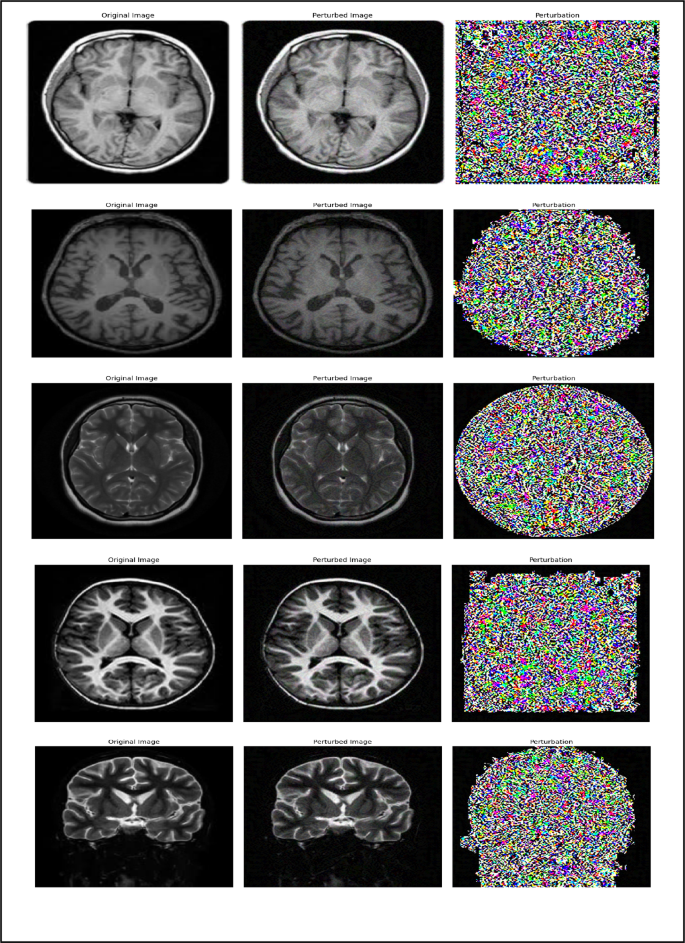

Adversarial attack methods

Research on adversarial attacks against machine learning models, particularly neural networks, has grown significantly, driven by the need to enhance their security and resilience26. Among the most widely used techniques for generating adversarial samples are Projected Gradient Descent (PGD) and the Fast Gradient Sign Method (FGSM). Both methods manipulate input data to deceive the model into producing incorrect predictions27, thereby exposing potential vulnerabilities28. Figure 2 illustrates normal MRI images, while Fig. 3 shows their perturbed counterparts generated using these adversarial techniques.

Normal MRI images.

Tumor MRI images.